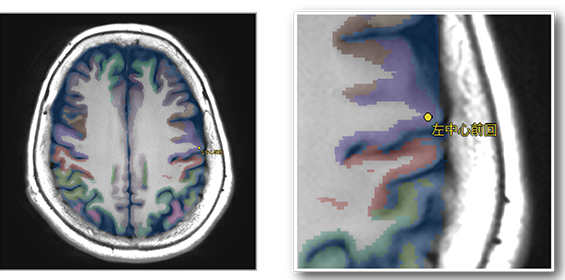

臓器セグメンテーション機能で認識した脳区域情報(111区域)を表示します。